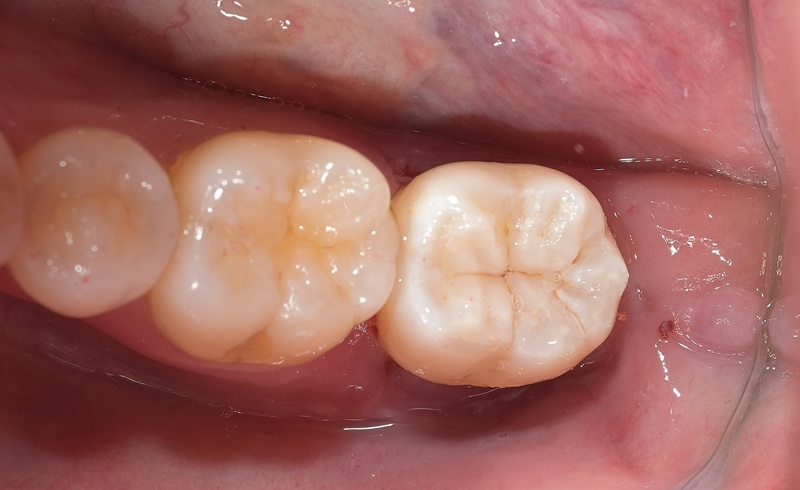

術後

| 治療名 | セラミックインレーによる虫歯の再治療症例 |

|---|---|

| 治療説明 |

過去に治療された銀歯が外れたとのことで来院されました。内部には古い接着剤の劣化と虫歯の再発が見られたため、しっかりと虫歯を除去し、セラミック製の詰め物(インレー)で再修復を行いました。 セラミックインレーは、天然歯に近い色調と自然な透明感を持っており、見た目が気になる部位にも適しています。 |

| 治療回数・期間 | 2回 |

| 副作用とリスク | ・保険診療の銀歯に比べて費用が高くなります。 ・治療直後は一時的に知覚過敏のような症状が出ることがありますが、ほとんどの場合は数日〜1週間程度で落ち着きます。 |

| 料金(税込) | 77,000円 |